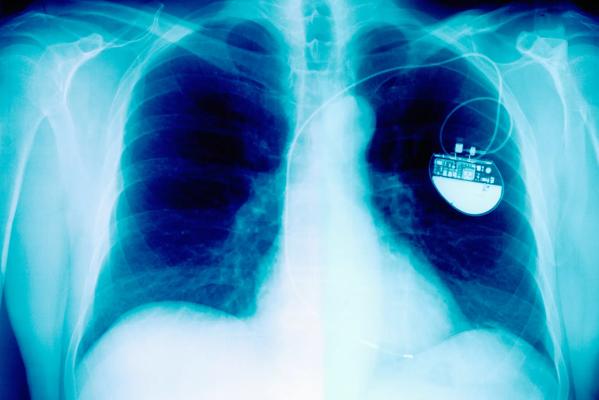

X-Ray Showing Pacemaker

Pacing leads are insulated wires that run from the heart to a pacemaker or implantable cardioverter-defibrillator. If there is an infection or malfunction, it is necessary to remove them. Lead extraction is a complicated procedure because it requires navigating tough scar tissue that holds the lead in place.